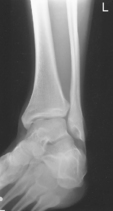

This is a frontal view of the entire ankle mortise and generally should not be a substitute for the routine AP or 45° oblique ankle.

• Recumbent, affected side down, affected knee partially flexed

• Dorsiflex foot 90° to leg if patient can tolerate.

• Place support under knee as needed for true lateral of foot and ankle.